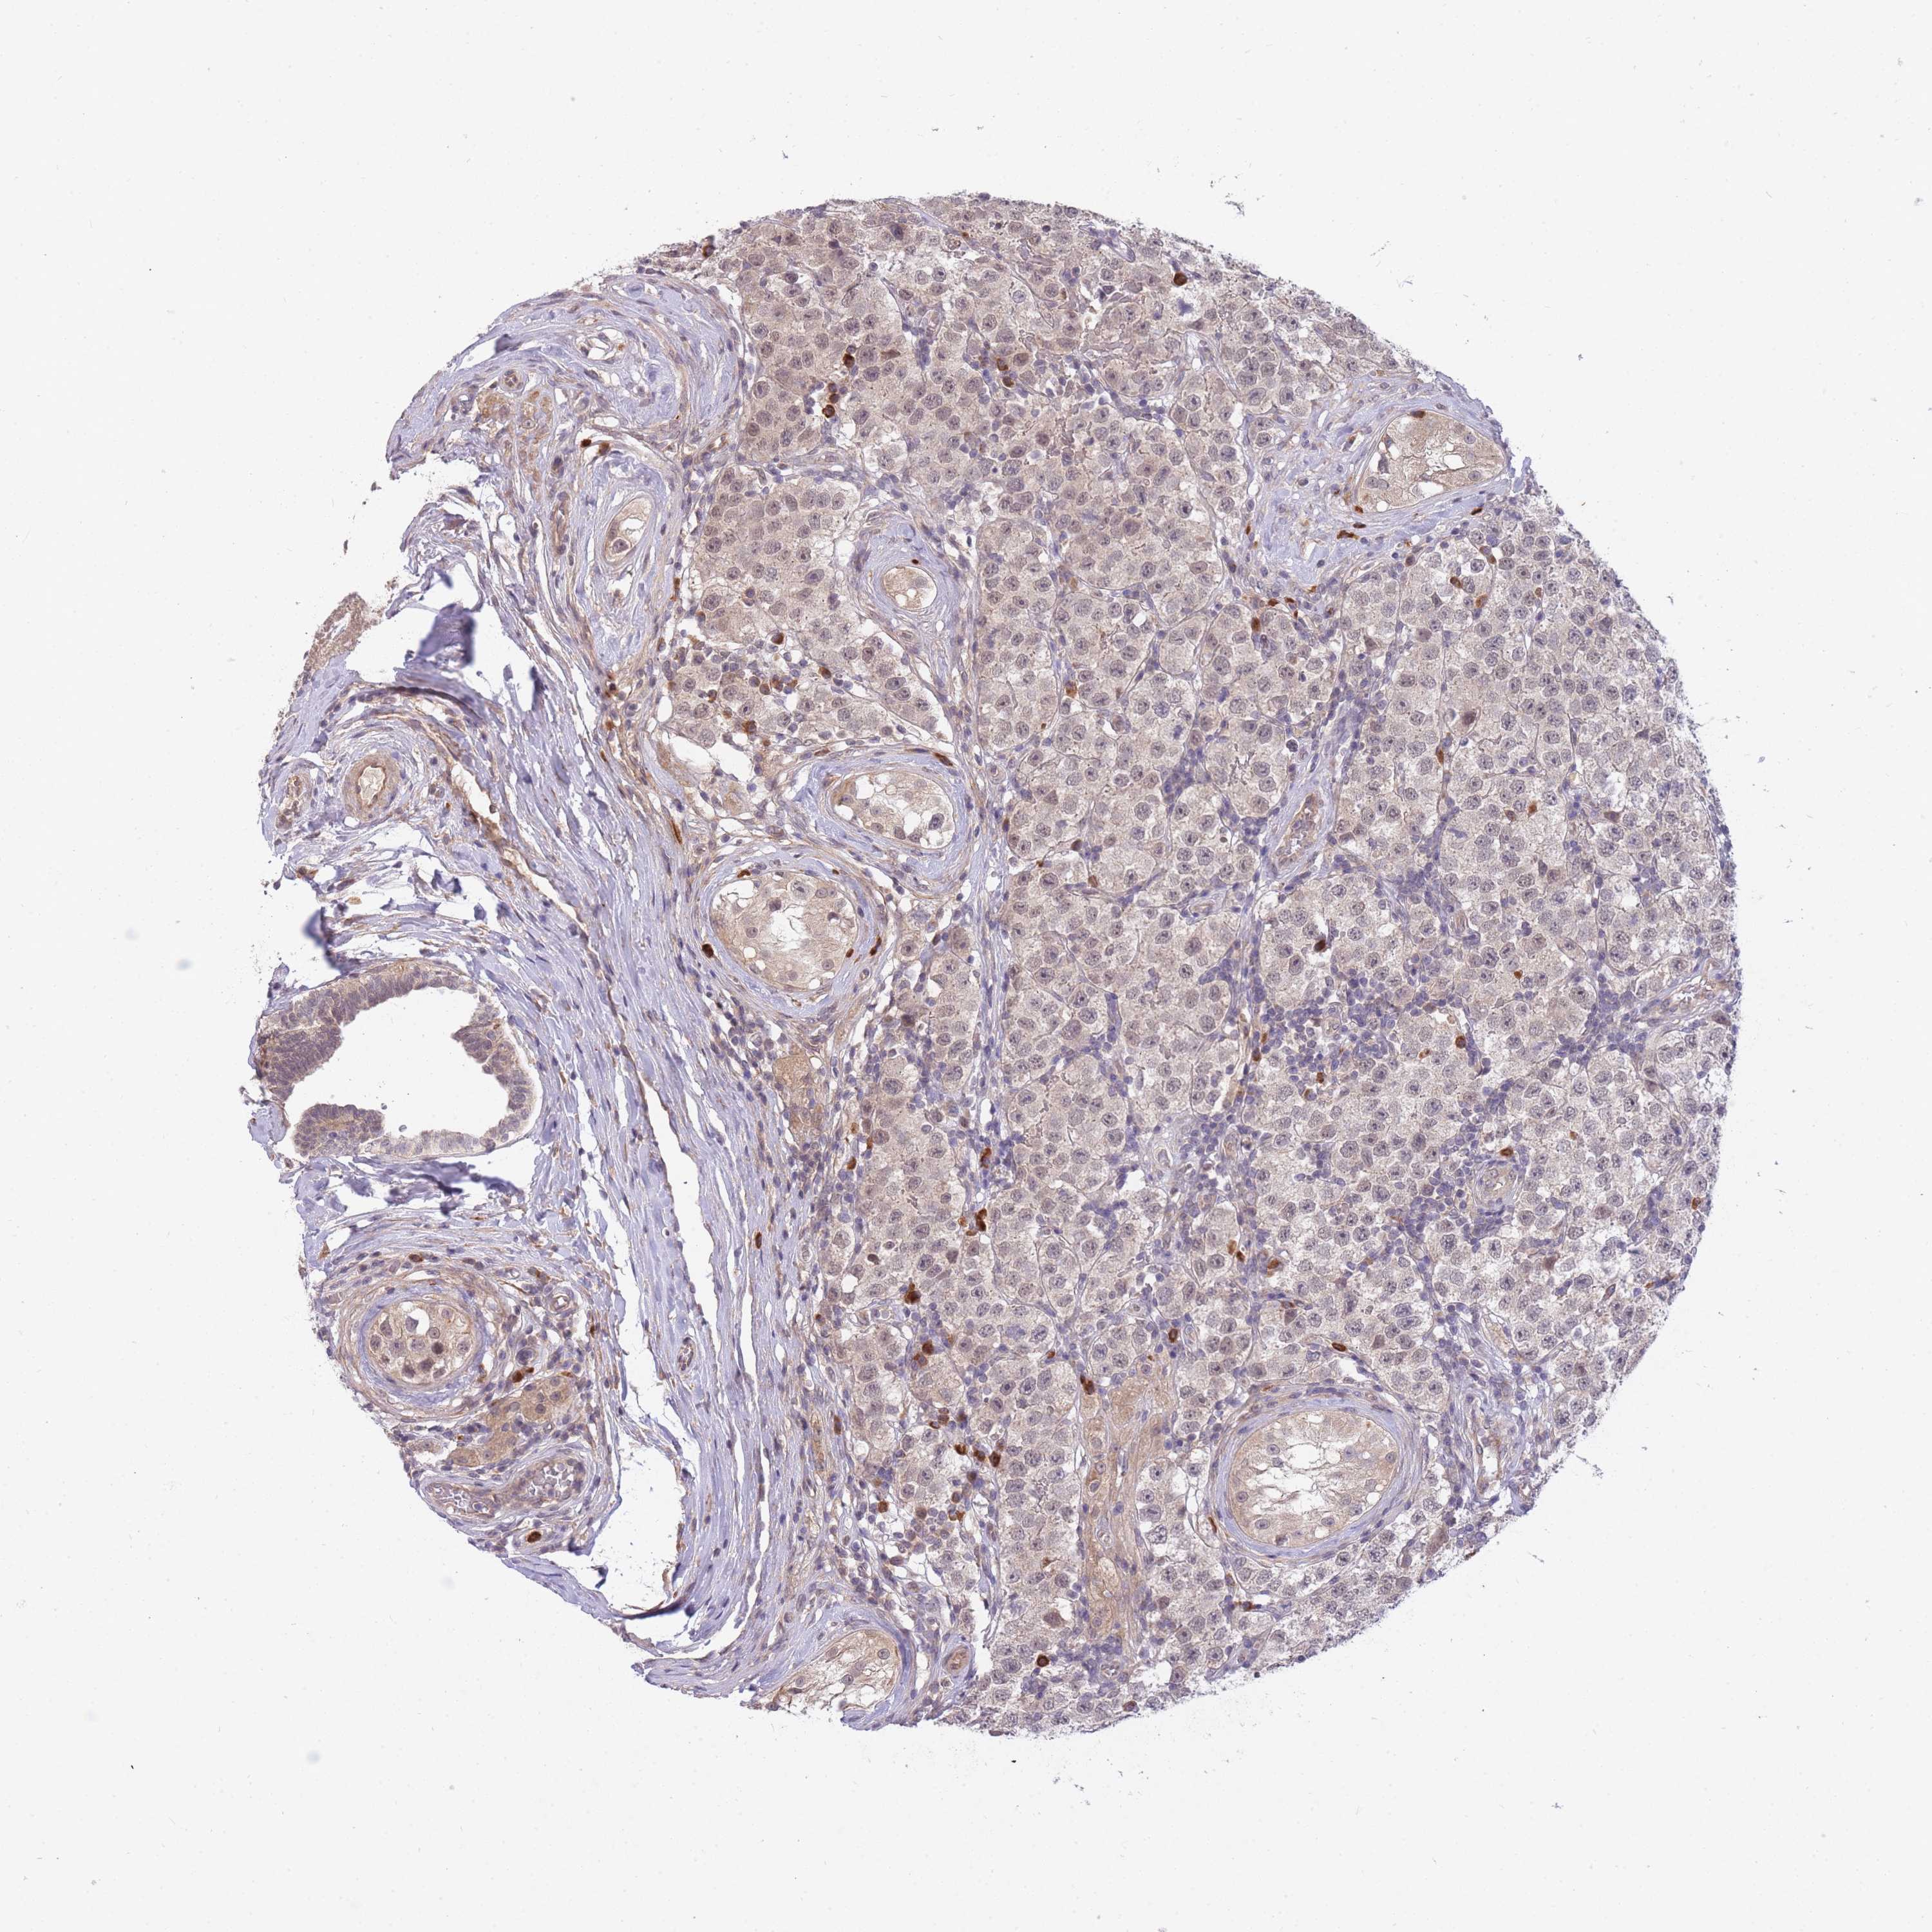

TESTIS CANCER - Protein expressioni

A mouse-over function shows sample information and annotation data. Click on an image to view it in a full screen mode. Samples can be filtered based on level of antibody staining by selecting one or several of the following categories: high, medium, low and not detected. The assay and annotation is described here.

Note that samples used for immunohistochemistry by the Human Protein Atlas do not correspond to samples in the TCGA dataset.

Antibody stainingi

Antibody staining in the annotated cell types in the current human tissue is reported as not detected, low, medium, or high, based on conventional immunohistochemistry profiling in selected tissues. This score is based on the combination of the staining intensity and fraction of stained cells.

Each image is clickable and will lead to virtual microscopy that enables deeper exploration of all samples and also displays staining intensity scores, fraction scores and subcellular localization as well as patient and tissue information for each sample.

Antibody HPA042733

Antibody CAB037186

Staining

High

Medium

Low

Not detected

Intensity

Strong

Moderate

Weak

Negative

Quantity

>75%

75%-25%

<25%

None

Location

Nuclear

Cytoplasmic/membranous

Cytoplasmic/membranous,nuclear

Carcinoma, Embryonal, NOS

Seminoma, NOS